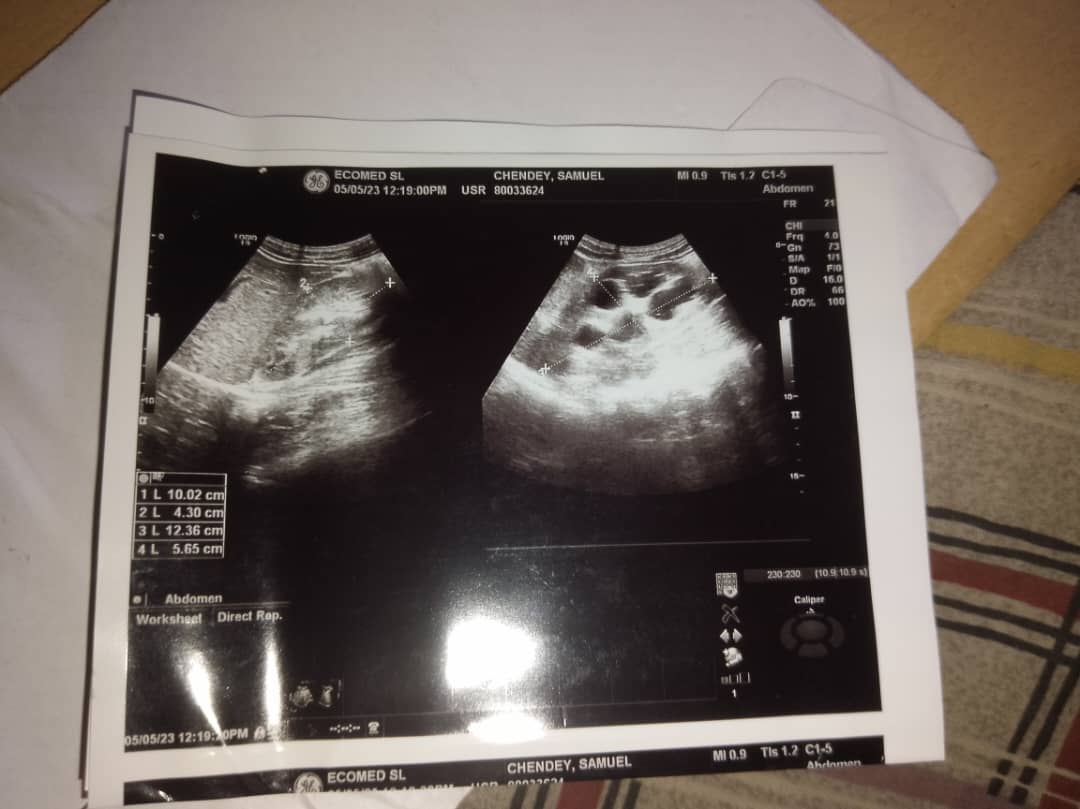

Chendey who is now in the second year of his course was diagnosed with kidney disease at the EcoMed Medical Center at Kingharman Road in Freetown. It was discovered in his scan result, that he has Kidney stones which one of the kidneys is bigger than the other.

Doctors advised that he get treatment as soon as possible, stating that Kidney disease develops from stages and it reaches certain stage where it will be very difficult to handle.